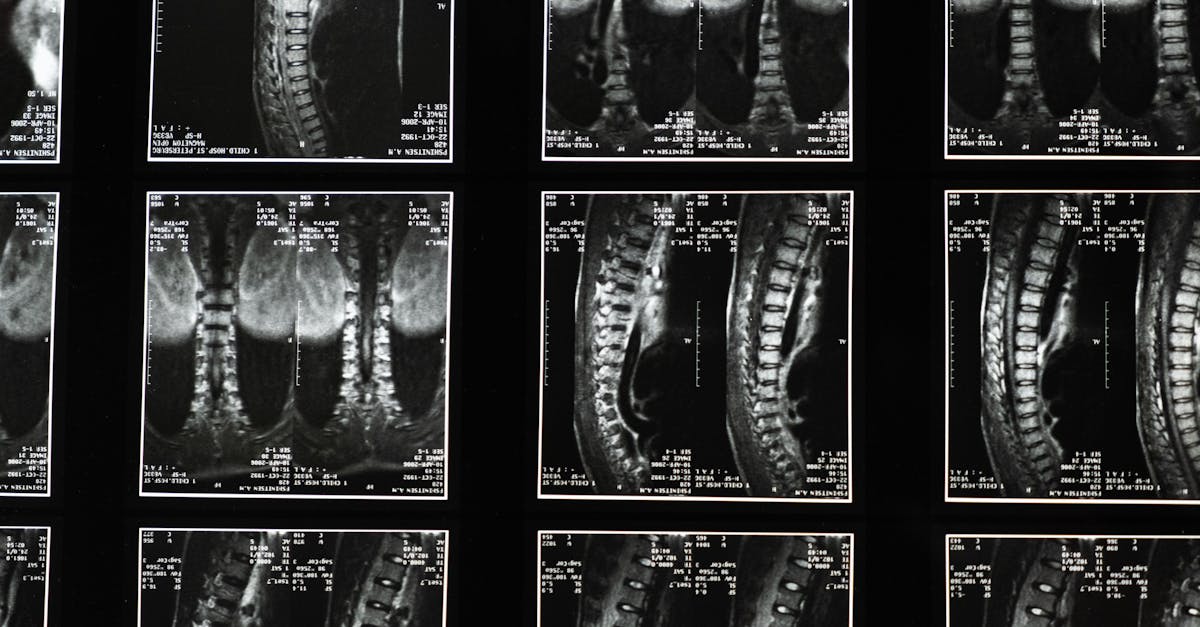

«`html ¿Siente ciática o dolor lumbar debilitante? Pulse Align ofrece un enfoque innovador para el alivio del dolor lumbar mediante una reevaluación holística que enfatiza la salud neuromuscular y la mejora de la postura. Este artículo explora técnicas efectivas para combatir el dolor de ciática mediante prácticas detalladas que se centran en la rehabilitación, ejercicios de fortalecimiento del core y ajustes diarios como técnicas adecuadas de levantamiento y ayudas ergonómicas. La ciencia detrás de las técnicas holísticas Pulse Align emplea un enfoque único que combina el fortalecimiento del core con ejercicios específicos para el dolor lumbar. Abordar problemas como hernias discales, estenosis espinal y síndrome piriforme requiere un enfoque integral tanto en el sistema físico como en el nervioso. Se emplean técnicas como la inclinación pélvica y los ejercicios de tronco para aliviar el dolor y promover la recuperación, fomentando la simetría muscular dinámica y estableciendo un equilibrio natural. Ejercicios efectivos para el dolor lumbar. Incorporar estiramientos para el dolor lumbar en tu rutina es fundamental. Estiramientos suaves, como el estiramiento de rodillas al pecho, pueden aliviar la tensión en la región lumbar y mejorar la flexibilidad. Combinarlos con ejercicios de fortalecimiento del core, como puentes y planchas, puede reforzar significativamente la estabilidad, reduciendo los síntomas durante actividades como el dolor lumbar al agacharse. Optimiza tu entorno y tus movimientos diarios. Ya sea en casa o en el trabajo, crear un entorno adecuado ayuda a corregir la postura. Utilizar una silla ergonómica puede ayudar a mantener la alineación de la columna vertebral al estar sentado durante períodos prolongados, mientras que implementar posiciones estratégicas para dormir para el dolor de espalda puede promover un descanso reparador. Además, seguir las técnicas adecuadas para levantar objetos durante las tareas manuales puede prevenir el agravamiento de la zona lumbar.

- La técnica aplicada en TAGMED implica el uso de fuerzas de tracción controladas y progresivas sobre la columna vertebral. Este método aumenta el espacio entre las vértebras, reduciendo eficazmente la presión sobre los discos intervertebrales y las raíces nerviosas. Además, promueve una mejor circulación de líquidos en la zona afectada, esencial para optimizar el aporte de nutrientes a los discos. Este proceso contribuye a reducir la inflamación y aliviar el dolor, ofreciendo una alternativa fiable y no invasiva para quienes sufren de dolor de espalda crónico.

Uno de los aspectos más atractivos de la terapia de descompresión espinal de TAGMED es su potencial para aliviar el dolor crónico y los síntomas asociados a la estenosis espinal y la protrusión discal. Al reducir la presión nerviosa y mejorar la circulación de líquidos alrededor de los discos, muchos pacientes experimentan una recuperación más rápida y una mejor calidad de vida. Esta modalidad de tratamiento no invasiva puede ser una solución eficaz para quienes sufren molestias debido a la enfermedad degenerativa del disco o la artrosis facetaria. Al comparar la tecnología de descompresión neurovertebral de TAGMED con otros tratamientos comunes, los beneficios se hacen evidentes. A diferencia de los analgésicos o las inyecciones de corticosteroides, que suelen provocar efectos secundarios, el enfoque de TAGMED minimiza los riesgos relacionados con la medicación y evita por completo las intervenciones invasivas. Para los pacientes que buscan una recuperación más rápida, la eficacia y la seguridad de la descompresión espinal la convierten en la opción preferida.